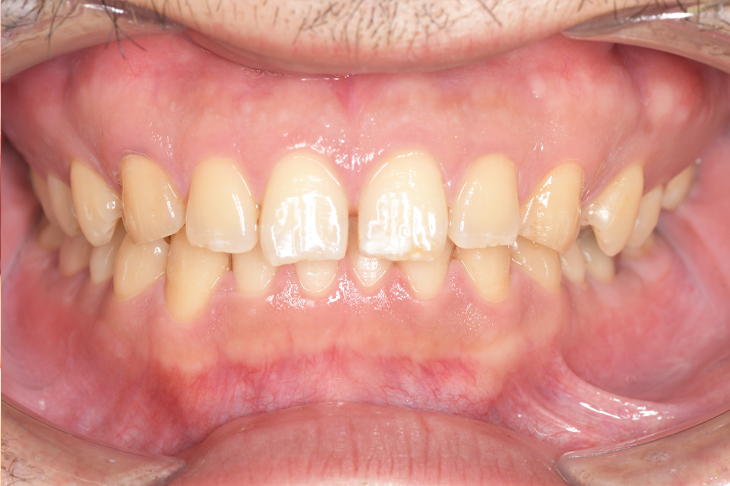

CASE 11

Before

After

基本情報

| 年齢・性別 | 32歳・男性 |

| 主訴 | 歯石をとりたい |

| 治療内容 | スケーリング |

| 治療期間 | 30分 |

| 治療費 | 1,500円(保険診療) |

| リスク・副作用 | 知覚過敏、歯肉退縮、出血 |

| 治療方針 | 今後も定期的にクリーニングを行っていきます。 |